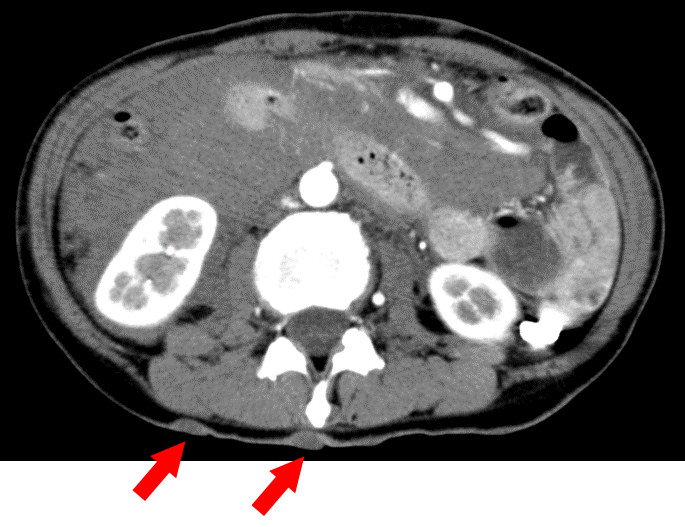

50歳代女性 腹痛、ショック:

• SMAの異常拡張

• 腸間膜主体に血腫

• 皮膚に多発結節()